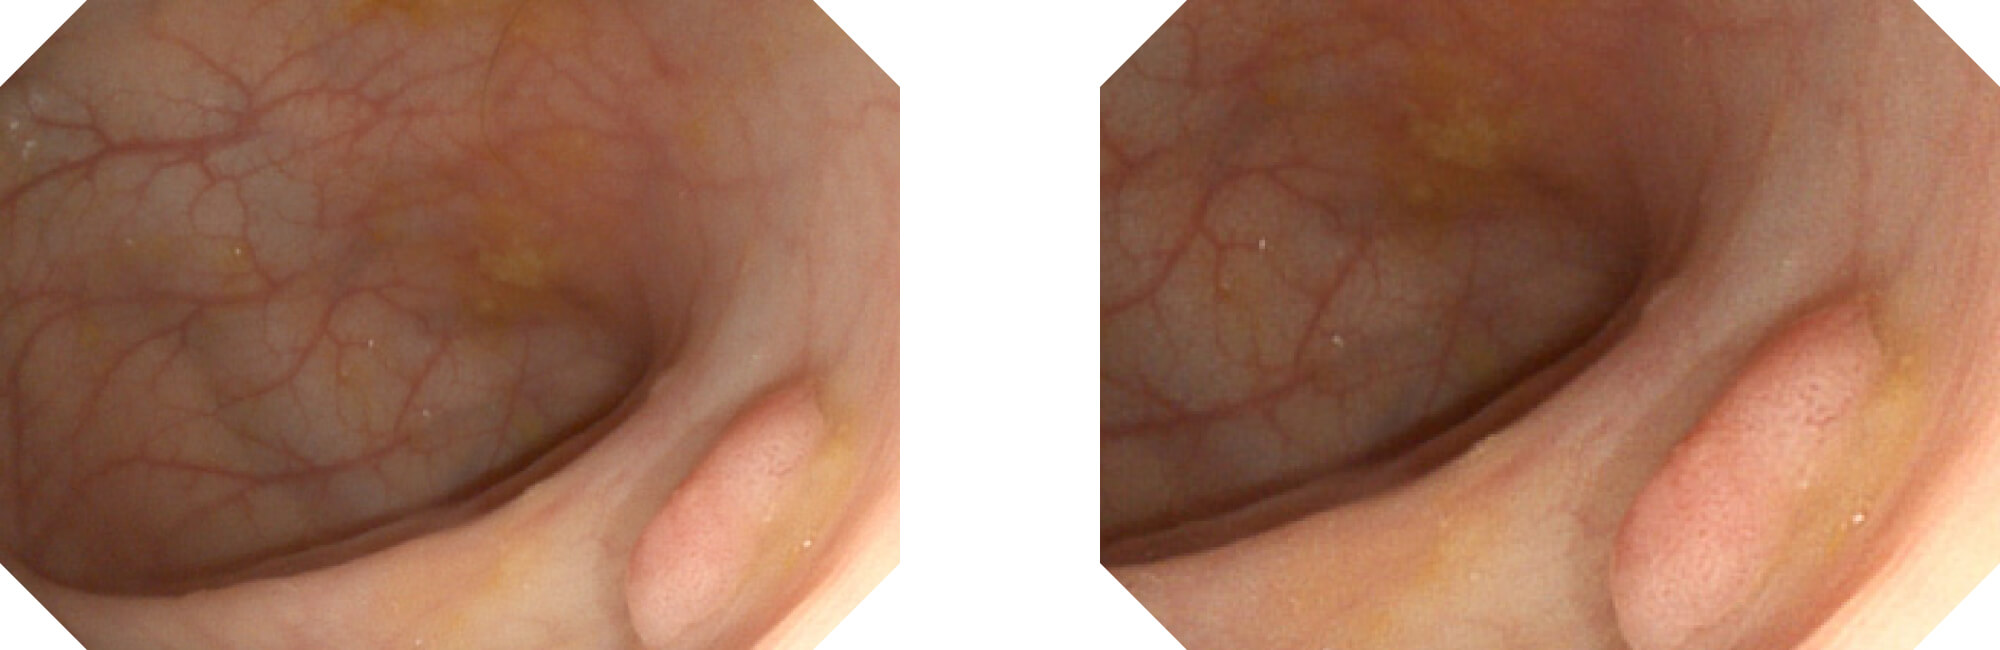

高清数字信号结合构造强调和色彩增强,多重图像处理技术能让每一个图像都清晰可见。

构造强调

色彩增强

电子放大

利用了血红蛋白在不同波长吸收下系数不同的原理,设计的一种光学域滤波和数字域滤波结合的染色技术,既保证了图像亮度,又可增强黏膜血管的对比度,充分凸显早期病变的细微结构变化,为临床疾病的观察诊断提供更丰富的参考信息。